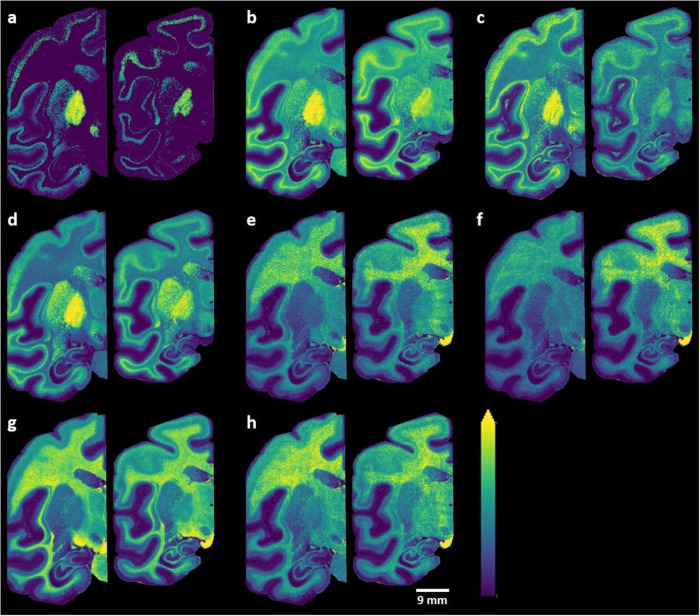

Long-chain hydroxylated and non-hydroxylated sulfatides within the GPe, GPi, and SNR regions were among the sulfatides that showed the largest differences between MPTP-treated and control brain sections (Fig. 4 and Supplementary Table 1). More specifically, the MPTP group showed a lower abundance of certain long-chain hydroxylated sulfatides with polyunsaturated chains, including SHexCer (t41:2), SHexCer (t42:2), SHexCer (t42:3), and SHexCer (t43:2), in the GPi, GPe, and SNR regions relative to the control group (Fig. 5a–d). In contrast, certain long-chain non-hydroxylated sulfatides, including SHexCer (d40:1), SHexCer (d40:2), SHexCer (d42:1), and SHexCer (d41:1), were present at higher levels in multiple brain regions, e.g., GPi, GPe, and SNR, in the MPTP group when compared to the control group (Fig. 5e–h and Supplementary Table 2). The distributions of several sphingolipids and glycerophospholipids that did not display significant changes between the control and MPTP groups were also recorded (Supplementary Fig. 5).

Fig. 5. MALDI-MS ion distribution images of sulfatides that showed significant differences between control (left) and MPTP-lesioned (right) brain sections.

a [SHexCer (t41:2)-H]−, b [SHexCer (t42:2)-H]−, c [SHexCer (t42:3)-H]−, d [SHexCer (t43:2)-H]−, e [SHexCer (d40:1)-H]−, f [SHexCer (d40:2)-H]−, g [SHexCer (d42:1)-H]−, h [SHexCer (d41:1)-H]−. Ion distribution images are scaled to the maximum intensity of each individual ion. Lateral resolution of the MALDI-MSI images is 150 µm and all of the ion images were RMS-normalized.